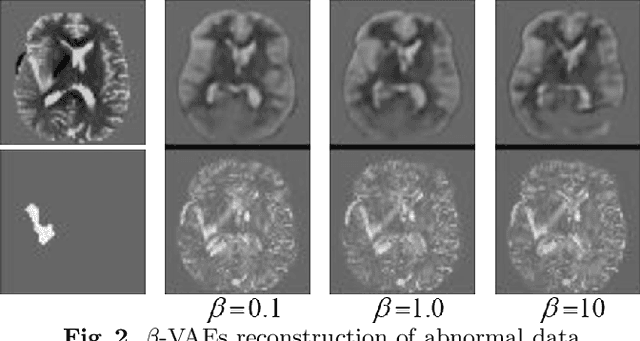

Abstract:Variational Auto-Encoders (VAEs) have shown great potential in the unsupervised learning of data distributions. An VAE trained on normal images is expected to only be able to reconstruct normal images, allowing the localization of anomalous pixels in an image via manipulating information within the VAE ELBO loss. The ELBO consists of KL divergence loss (image-wise) and reconstruction loss (pixel-wise). It is natural and straightforward to use the later as the predictor. However, usually local anomaly added to a normal image can deteriorate the whole reconstructed image, causing segmentation using only naive pixel errors not accurate. Energy based projection was proposed to increase the reconstruction accuracy of normal regions/pixels, which achieved the state-of-the-art localization accuracy on simple natural images. Another possible predictors are ELBO and its components gradients with respect to each pixels. Previous work claimed that KL gradient is a robust predictor. In this paper, we argue that the energy based projection in medical imaging is not as useful as on natural images. Moreover, we observe that the robustness of KL gradient predictor totally depends on the setting of the VAE and dataset. We also explored the effect of the weight of KL loss within beta-VAE and predictor ensemble in anomaly localization.